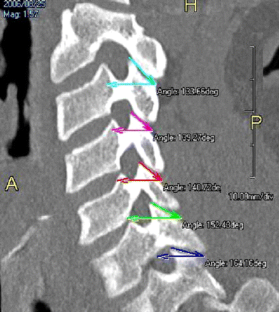

The articular facets of the cervical spine have been well addressed; however, little information is available on the relationship of the superior facets of the cervical spine to traumatic dislocation in the literature. Morphometric analyses of the superior facets of 30 dried cervical spines from C3 to C7 were performed to determine any morphological differences. The angle of the superior facet with respect to the transverse plane was also measured on computed tomography (CT) scans of 30 patients having neck injury without fracture/dislocation. The vertical and surface lengths of the superior facet were significantly lower (P < 0.01) at C6–C7 levels than at C3–5 levels. The anteroposterior diameter of the superior facet was smaller (P < 0.05) at C6 and C7 levels compared to C3–5 levels. Although the superior facet joint surface is in a more coronal orientation in lower cervical vertebrae, the inclination of the superior facet is more horizontal relative to the transverse plane when measured in vivo. A combination of lower height, smaller anteroposterior diameter of the superior facet, and a more horizontally oriented superior facet at C6 and C7 levels in vivo may explain the predilection of translation relative to one another in the lower cervical spine.

Fig. 1

Fig. 2

Fig. 3